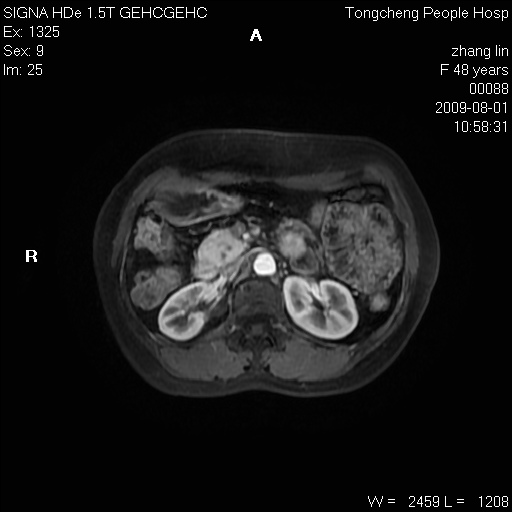

女,48岁。健康体检,彩超发现右肾占位性病变。平素健康。

临床诊断:右肾占位性病变,性质待定(囊肿?肿瘤?)。

上中腹部mr平扫+增强扫描,图像如下:

右肾上极见一类圆形病灶,t1wi呈等信号t2wi呈等高混杂信号,三期增强无强化,边界清---考虑囊肿出血。

同反相位均表现为等信号,病变无强化,考虑含蛋白的囊肿可能,弥散加权相或许有些帮助,

肝囊肿

慢性胆囊炎